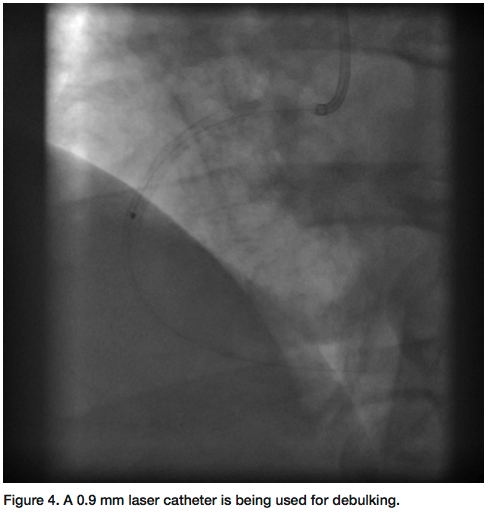

Percutaneous intervention of the RCA was performed via the right radial approach using a 6 French (Fr) MAC 3.0 guide catheter (Medtronic). A 300 cm Kinetix wire (Boston Scientific) and subsequently a hydrophilic PT II Graphix (Boston Scientific) wire along with a 1.25mm x 10mm over-the-wire balloon were used to cross the CTO (Figure 3). After the initial crossing into the proximal cap, we could not advance the wire further. With the hope of creating a channel through the proximal cap, a 0.9 laser catheter (Spectranetics